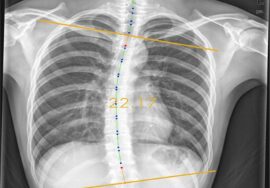

يُعد حزام اعوجاج العمود الفقري أحد أهم أدوات علاج اعوجاج العمود الفقري عند الأطفال والمراهقين، إذ يساعد على تقليل الانحناء ودعم تصحيح العمود الفقري خلال فترة النمو. ومع ذلك، قد يلاحظ بعض الأهل أن طفلهم يشعر بألم في الضلوع بعد بدء استخدام الحزام، وهنا تبدأ الأسئلة:

لماذا يشعر الطفل بألم في الضلوع عند استخدام حزام اعوجاج العمود الفقري؟

1. الضغط التصحيحي على مناطق محددة

الحزام يعمل عن طريق توجيه قوة محسوبة على مناطق معينة من الضلوع أو القفص الصدري لإعادة تنظيم العمود الفقري.

لذلك، قد يحدث شعور بالشد أو الانزعاج، خصوصًا عند البداية.